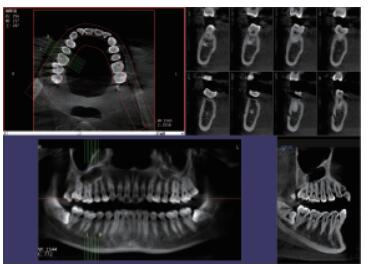

三維重建任意斷層

專有三維重建算法,可提供任意位置高清斷層影像。

高清口腔全景影像

通過三維容積影像,提取高清口腔全景影像。

多平面組合重建

可同時觀察軸向面、冠狀面和矢狀面圖像,方便臨床診斷。